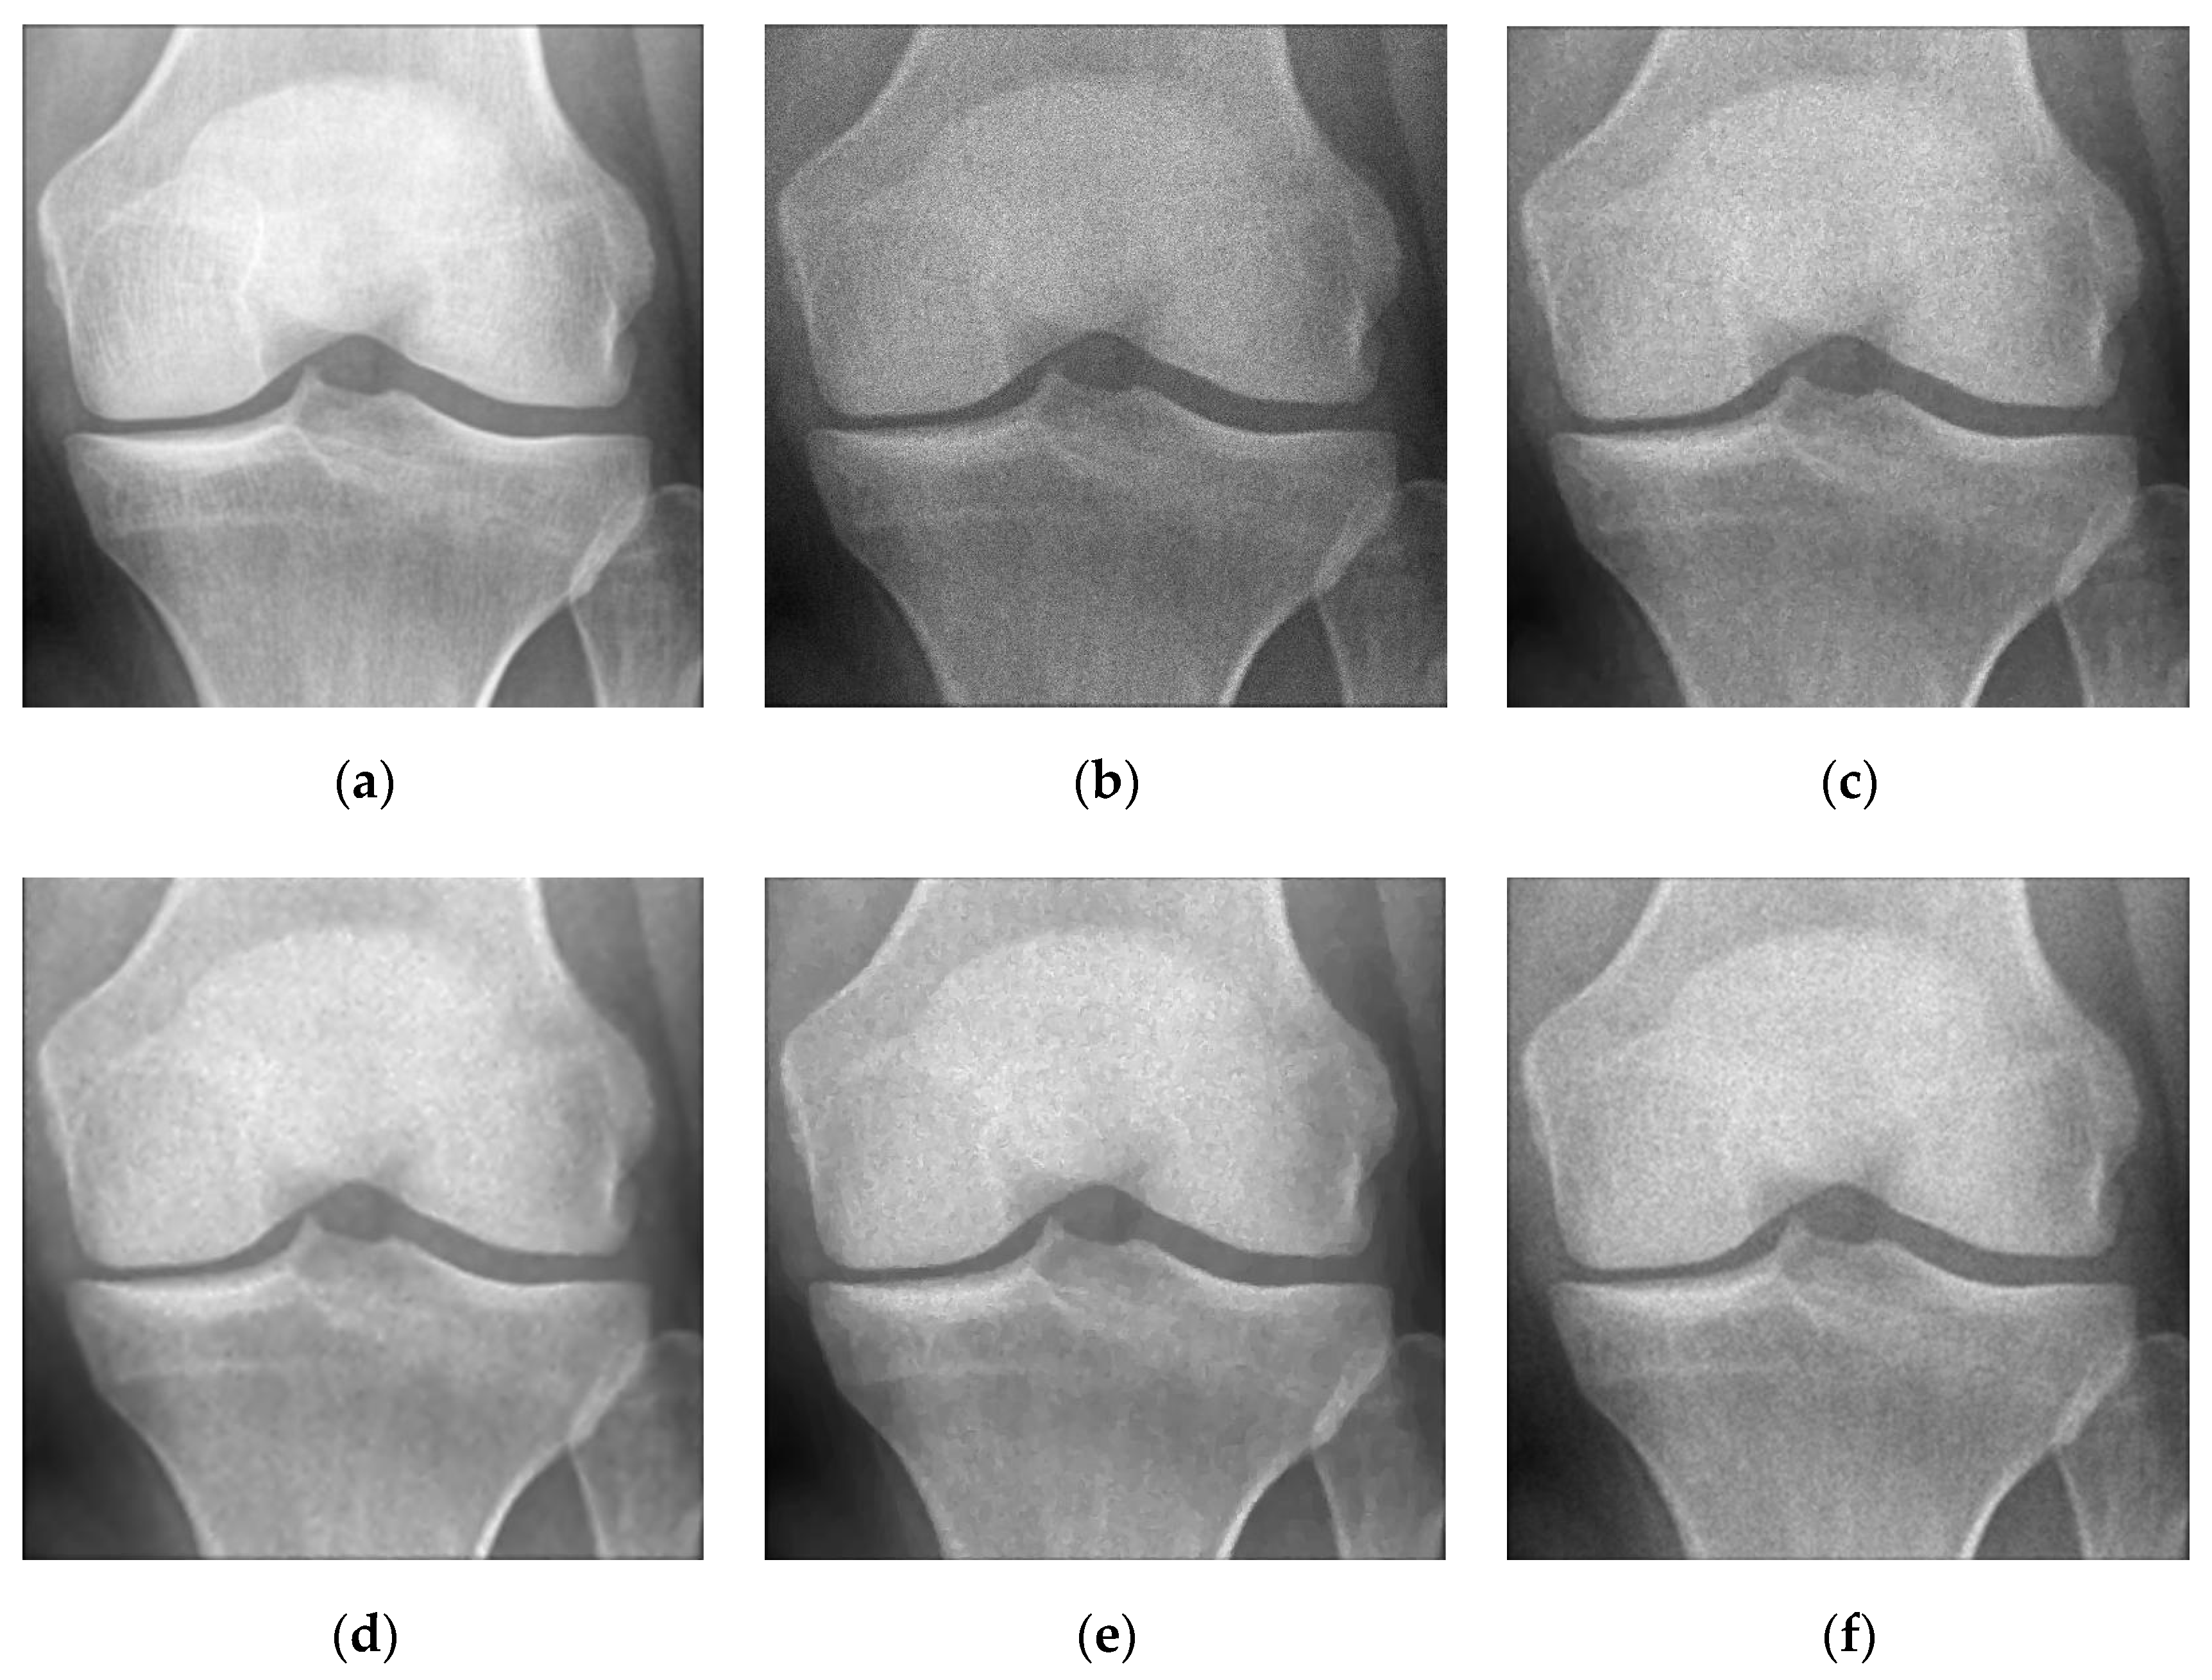

5.2. Numerical Simulations on Medical Images

5.2.2. Different Methods

- Partial Differential Equation Method

- ADMM Method

5.2.3. Comparison with Other Variational Models